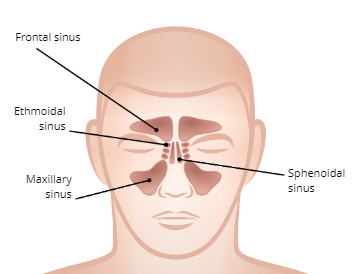

SInuses

four pairs of hollow spaces in the skull that open into the nasal cavity

Functions of the Sinuses

1. Moistens and filters air

2. Regulate air temperature

3. Provide voice resonance